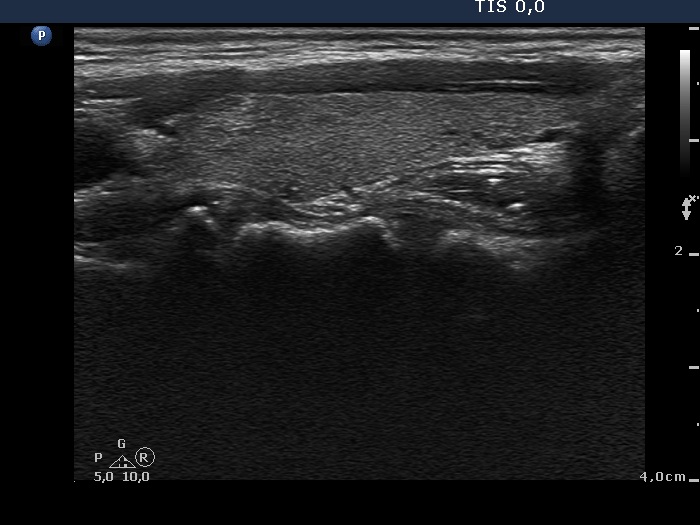

Differential diagnostic of thyroid cysts - Case 10. (ultrasonographic picture 6)

Left lobe, longitudinal view.